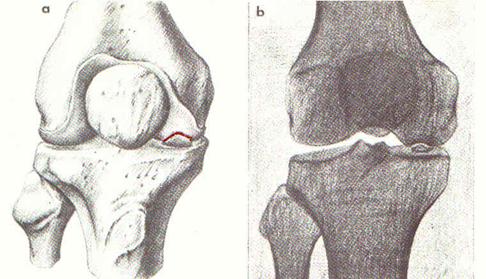

Osteocondrite dissecante (m. di Konig)

Si tratta di una necrosi parcellare che interessa solo una piccola parte, lenticolare, della cartilagine articolare e della corrispondente spongiosa subcondrale dell’epifisi distale del femore o dell’omero.

Compare in età giovanile, in individui robusti, in ginocchia molto sollecitate.

Il frammento osseo, in preda a fenomeni necrotici, si demarca nettamente dal tessuto osteocartilagìneo circostante fino a distaccarsi e cadere libero. nell’articolazione (“topo” articolare).

La sintomatologia nella fase prodromica è intermittente, il dolore è scarsamente localizzato, coesistono idrartri recidivanti ed ipotrofia del quadricipite.

Nella fase successiva, quando cioè si è verificato il distacco del cosiddetto “topo” articolare, possono osservarsi fenomeni di blocco dell’articolazione, con impossibilità — se si tratta del ginocchio — a flettere ed estendere la gamba